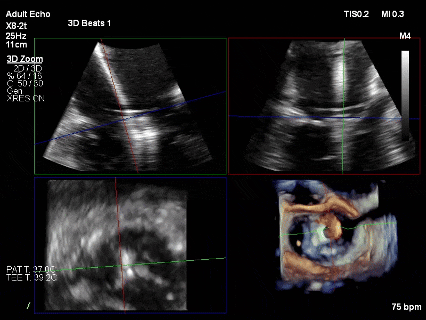

第二枚XTR植入后瓣口平均压差3mmHg

3D-Zoom下观察组织桥稳定,内侧残余脱垂

超声评估后决定释放第二枚夹子,继续在其内侧植入第三枚XTR

最终结果3D-Zoom-color显示组织桥稳定,原脱垂区域前后叶对合部分的脱垂已消除,反流降至1+以下

夹子释放Bi-com切面显示残余反流情况

肺静脉收缩期逆流消失,频谱形态基本恢复正常